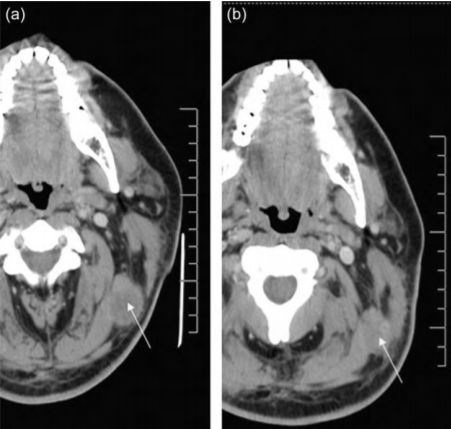

2008 年,美國拉什大學(xué)醫(yī)學(xué)中心的研究人員將外源擴(kuò)增的 NK 異體細(xì)胞注入到黑色素瘤患者體內(nèi),結(jié)果發(fā)現(xiàn),注入注入 NK 細(xì)胞后,該患者左上頸部腫瘤的體積明顯降低(從 3.15cm×2.54cm 減小至 2.46cm×1.76cm)。同時,該研究也為外源擴(kuò)增的 NK 異體細(xì)胞是否可以大規(guī)模應(yīng)用于治療黑色素瘤提供了一定的理論依據(jù)。

▲NK細(xì)胞治療前后對比圖